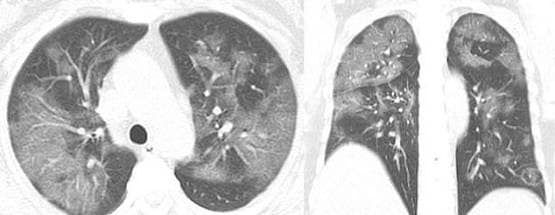

ये दूसरी तस्वीर 54 वर्षीय एक अन्य महिला की है. यहां भी तस्वीरें लगभग वैसी ही कहानी बयां कर रही हैं. यह महिला चीन के सिचुआन प्रांत की रहने वाली हैं.

PHOTO: RSNA